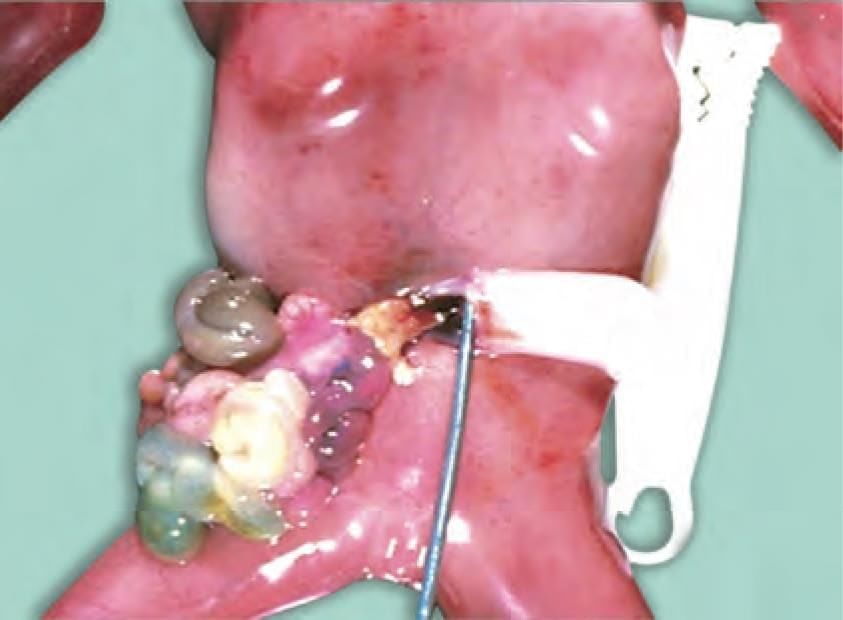

Identify the congenital anomaly shown in the newborn baby: (NEET-PG 2022)